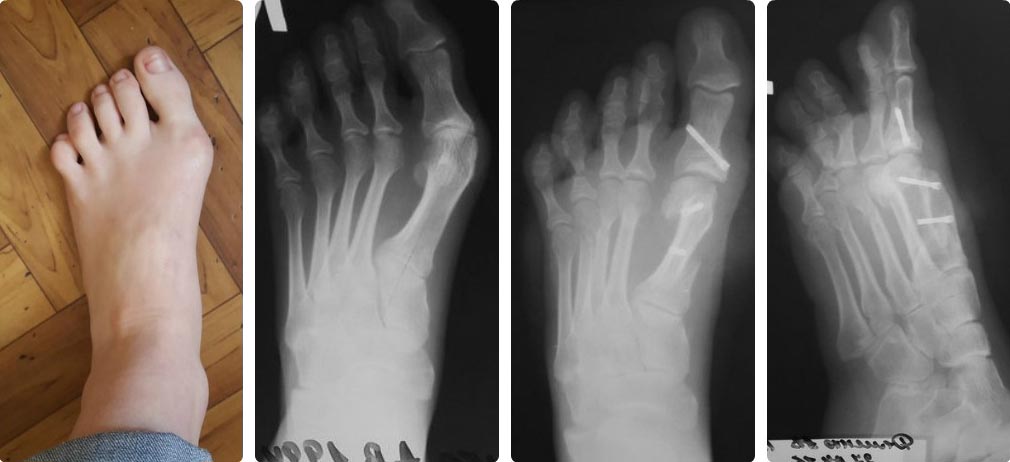

Оперировал девочку с выраженным египетским типом стопы. Год назад ей в

другой клинике проведено оперативное лечение операция Шеде с рецидивом.

Диагноз: вальгусная деформация 1 п 2 степени. рецидив. Молоткообразная

деформация 2,4 пальцев, подлежащий 3 палец. При осмотре омозолелость под

головкой 1 плюсневой. Омозолеость по внутренней части основной

фаланги, пальпаторно низкое расположение головки 4 плюсневой кости,

глоловка прямо под кожей. Клинически этот же палец молоткообразный. 2

палец тоже деформирован, но не как молоток, а не достигается подошвенное

сгибание, и вершина деформации как бы на уровне

плюснефалангового сустава, плюс отклонен кнаружи. 3 и 4 пальцы как бы

перекрещены На фото пальцы она расправила, как стала на стопу.

План был такой scarf Akin + tilt up4, остеотомия основания 4 основной

фаланги. Закрытая тенотомия разгибателей и поверхностного сгибателя

4п. В итоге, изначально, после завершения работы на 1 луче получилась

хорошая квадратная стопа. После dmmo 4 имхо нужно было заканчивать И еще

очень сильно плантаризировал плюсневую (чем может грозить?) Зачем- не

скажу, сам не понял как так распилил.

И это пол беды, далее что то так сказать увлекся радикализмом. Мысль

изначально была такова- засчет dmmo устранить отклонение малых пальцев,

и, учитывая, что хоть на 3 ей плюсневой и нет деформации, по снимкам она

длинновата В итоге выполнил остетомии dmoo 2,3,4 плюсневых. Тенотомии

2,3,4 разгибателей. Остетотомию основной фаланги 4 пальца Итог- та же

египетская стопа только с ровным пальцем((((! Чем может грозить? Давайте

обсудим !